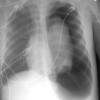

Blunt Chest Trauma

Pneumothorax

Album: Pneumothorax